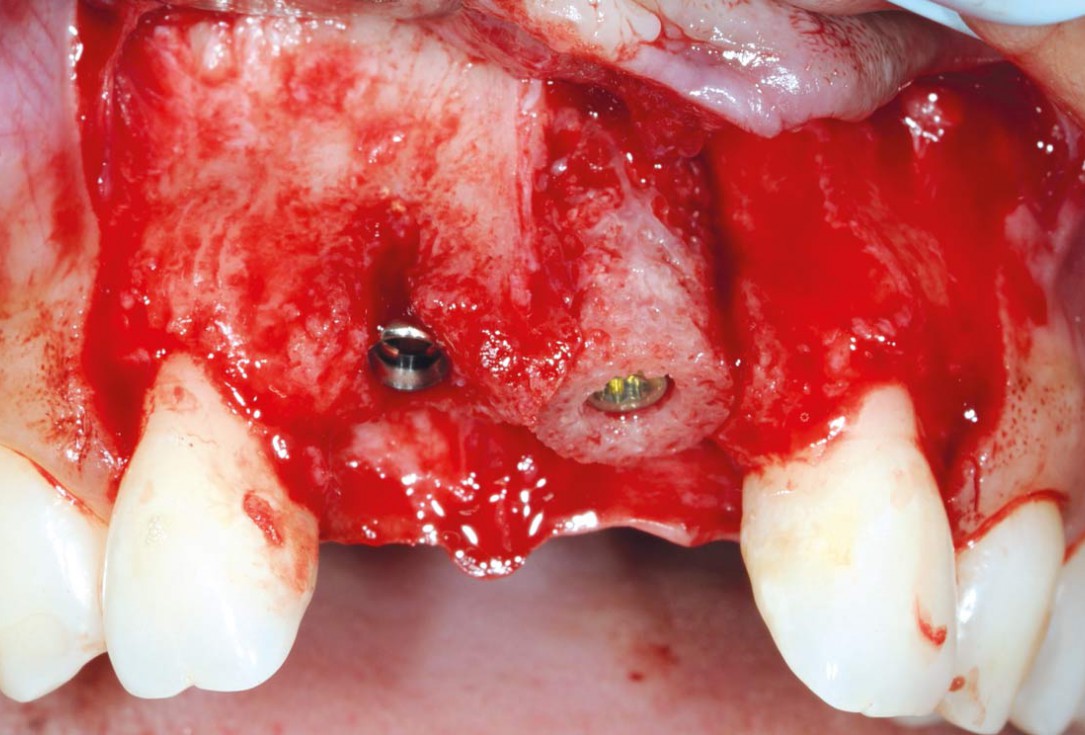

4/26 - Determine the defect size with the trephineBone augmentation in aesthetic zone with maxgraft® bonering - Dr. A. Patel